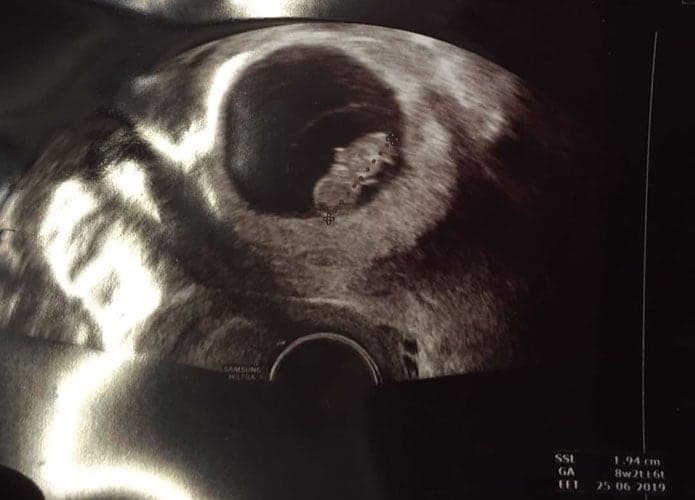

Ultraschallbilder aus dem 1. Trimester (1. SSW bis 12. SSW)

Im ersten Trimester sind die Ultraschallbilder meist noch schwer zu deuten. Oft erkennt man in den letzen Wochen des ersten Trimesters gut den Körper, den Kopf und die Gliedmaße. Das Geschlecht kann man in dieser Zeit meist noch nicht erkennen.